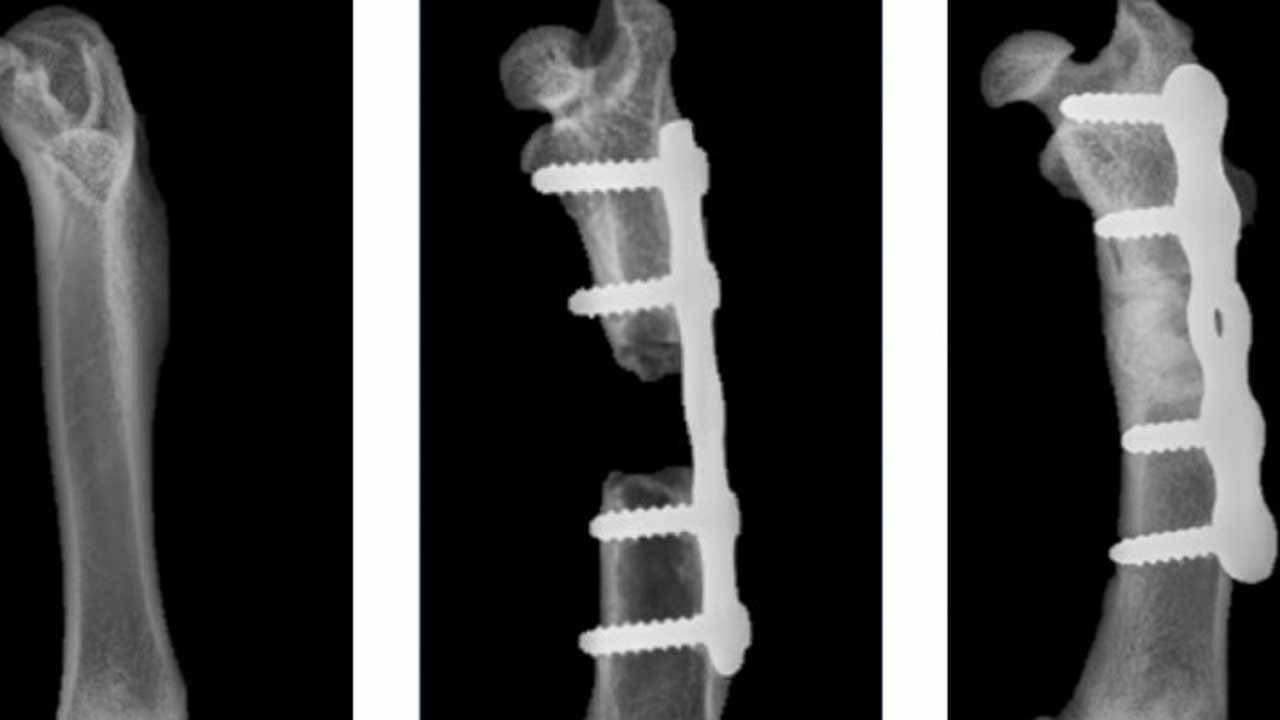

মূলত টিবি ও বোন ক্যান্সারের রোগীদের ক্ষেত্রে এই উদ্ভাবন উপকারী হবে বলে মনে করছেন ওই অধ্যাপক। তিনি জানান, ওই সব রোগীদের ক্ষেত্রে ক্ষতিগ্রস্ত অংশ বাদ দিয়ে দেওয়া ছাড়া কোনও উপায় থাকে না। আর ওই অংশে নতুন করে হাড় তৈরি হওয়ার কোনও আশাও থাকে না। অনেক সময় দুর্ঘটনায় আহত হলেও একই সমস্যা হতে পারে। এ ক্ষেত্রে চিকিৎসক নতুন পদ্ধতি ব্যবহার করতে পারেন। এতে কোনও ইনফেকশন হওয়ার সম্ভাবনাও নেই।